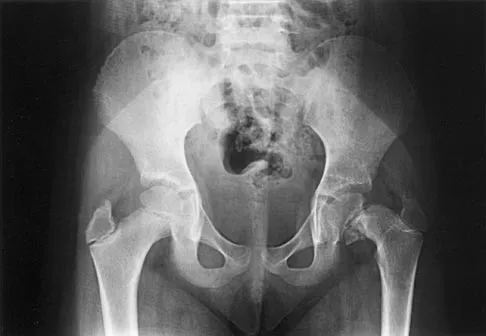

Which of the following choices best describes the fracture pattern shown in Figures 2a through 2c?

The fracture pattern shown in the radiographs is a fracture of the posterior column. The only line interrupted on the AP pelvis is the ilioischial line. The obturator oblique view shows that the iliopectineal line is intact as is the outline of the posterior wall. The iliac oblique view shows an interruption of the ilioischial line and an intact anterior wall. Therefore, this fracture is a fracture of the posterior column. Letournel E, Judet R: Fractures of the Acetabulum, ed 2. Berlin, Germany, Springer Verlag, 1993.